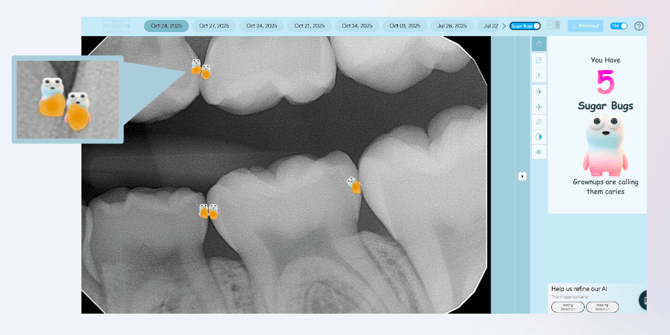

Sugar Bugs is a new enhancement in Second Opinion designed to make pediatric dental visits less intimidating for children. By replacing the traditional clinical caries UI with colorful, kid-friendly sugar bugs, dental staff can explain findings in a way that is engaging and easy for both children and their parents to understand.

Sugar Bugs Toggle: A new toggle labeled Sugar Bugs appears automatically in the top panel (next to the A|B icon) when a mixed dentition image is detected. By default, the toggle is off, showing the standard interface.

Activating Sugar Bugs: Turning the toggle on replaces traditional caries indicators with colorful sugar bugs, making it easier to explain findings to children.

Pediatric Only: The Sugar Bugs toggle is only available for pediatric bite wings and periapical images. It does not appear for adult images or in regions where regulatory clearance does not permit pediatric caries overlays.